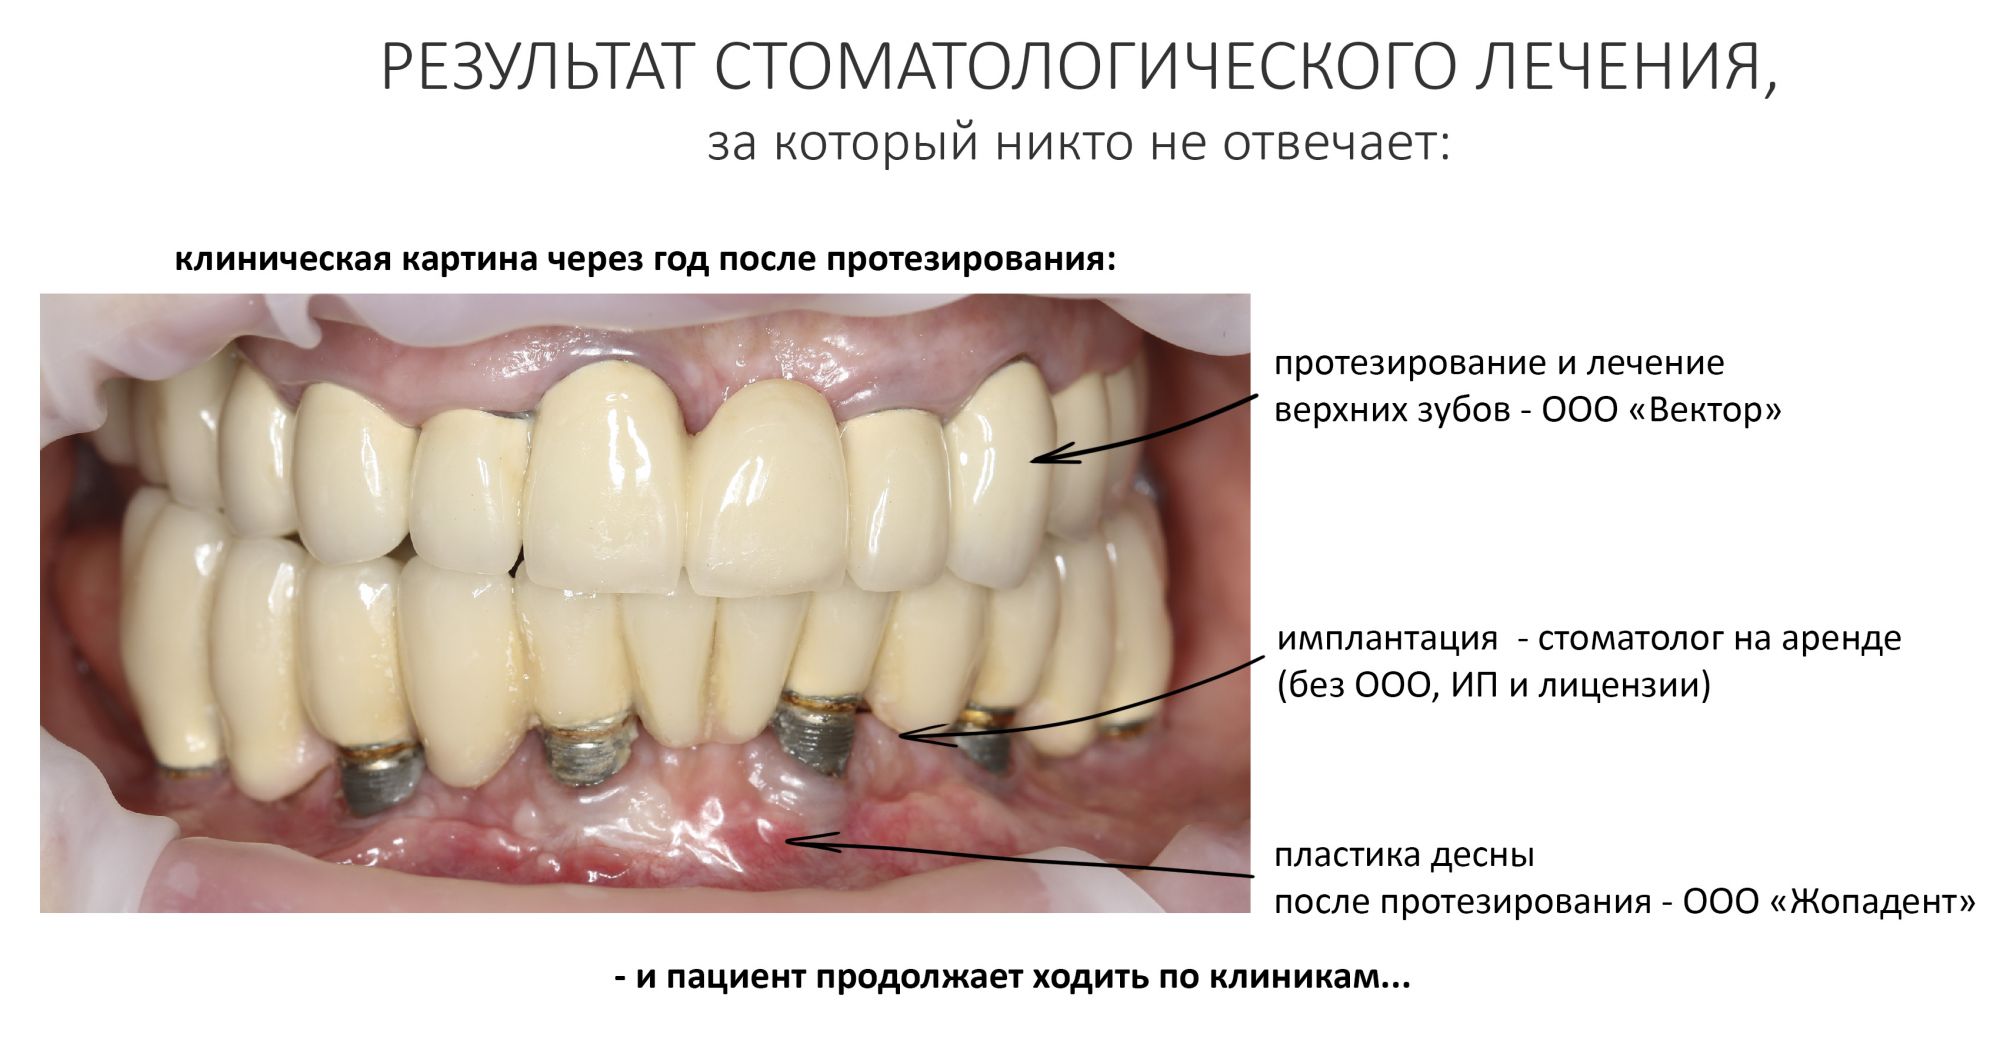

Честно признаюсь, я крайне отрицательно отношусь к т. н. «реферативной» практике, когда для решения одной клинической задачи пациент бегает из клиники в клинику. Например, имплантацию проводят в одной клинике, протезирование этих имплантатов — в другой, пластику десны делают в третьей и т. д. Это прикольно и весело ровно до того момента, пока не встает вопрос об ответственности за проведенное лечение, которое, как я уже написал, редко бывает быстрым и одноэтапным.

Реферативная практика — это еще ничего, поскольку она предполагает хоть какое-то взаимодействие с коллегами из других клиник. В свою очередь, я всегда настаиваю, чтобы пациент приезжал на консультацию вместе с направившим его доктором. Более того, я рекомендую этому доктору присутствовать (или даже участвовать) в предстоящей хирургической операции — в конце концов, зачем направлять, если можно научиться? Наконец, реферативная практика подразумевает полное и глубокое взаимодействие между специалистами, как если бы они работали в соседних кабинетах. Без этого условия достижение приемлемого результата лечения невозможно.

Намного страшнее ситуации, когда пациент сам находит себе докторов в разных клиниках, которым поручает решение одной клинической задачи. Например, он проводит имплантацию в нашей клинике, но протезировать имплантаты планирует в Мытищах, потому что там дешевле/друзья/ближе к дому. Пациент думает, что всех перехитрил и сэкономил целых пять тыщ. Но потом он возвращается к нам с периимплантитом из-за того, что дешевый дружбан-стоматолог рядом с домом при установке протезов натолкал под десну фиксирующий цемент.

Никто не спорит, бывает всякое, в т. ч. и ошибки. Но если ошибка произошла в нашей клинике, мы можем провести расследование, назначить виновных, раздать пиздюли и принять меры по недопущению ошибки в будущем. В таких случаях наш пациент вправе рассчитывать на компенсацию — я не скрою, прецеденты имеются. Но должны ли мы нести ответственность за рукожопое протезирование установленных нами имплантатов? И за сами имплантаты, если рукожопое протезирование привело к их утрате или периимплантиту?

У семи нянек дитя без глаза. У четырнадцати — без двух. Отличная поговорка. Когда за одну и ту же работу несут ответственность несколько врачей или клиник — считай, что за неё никто не отвечает.